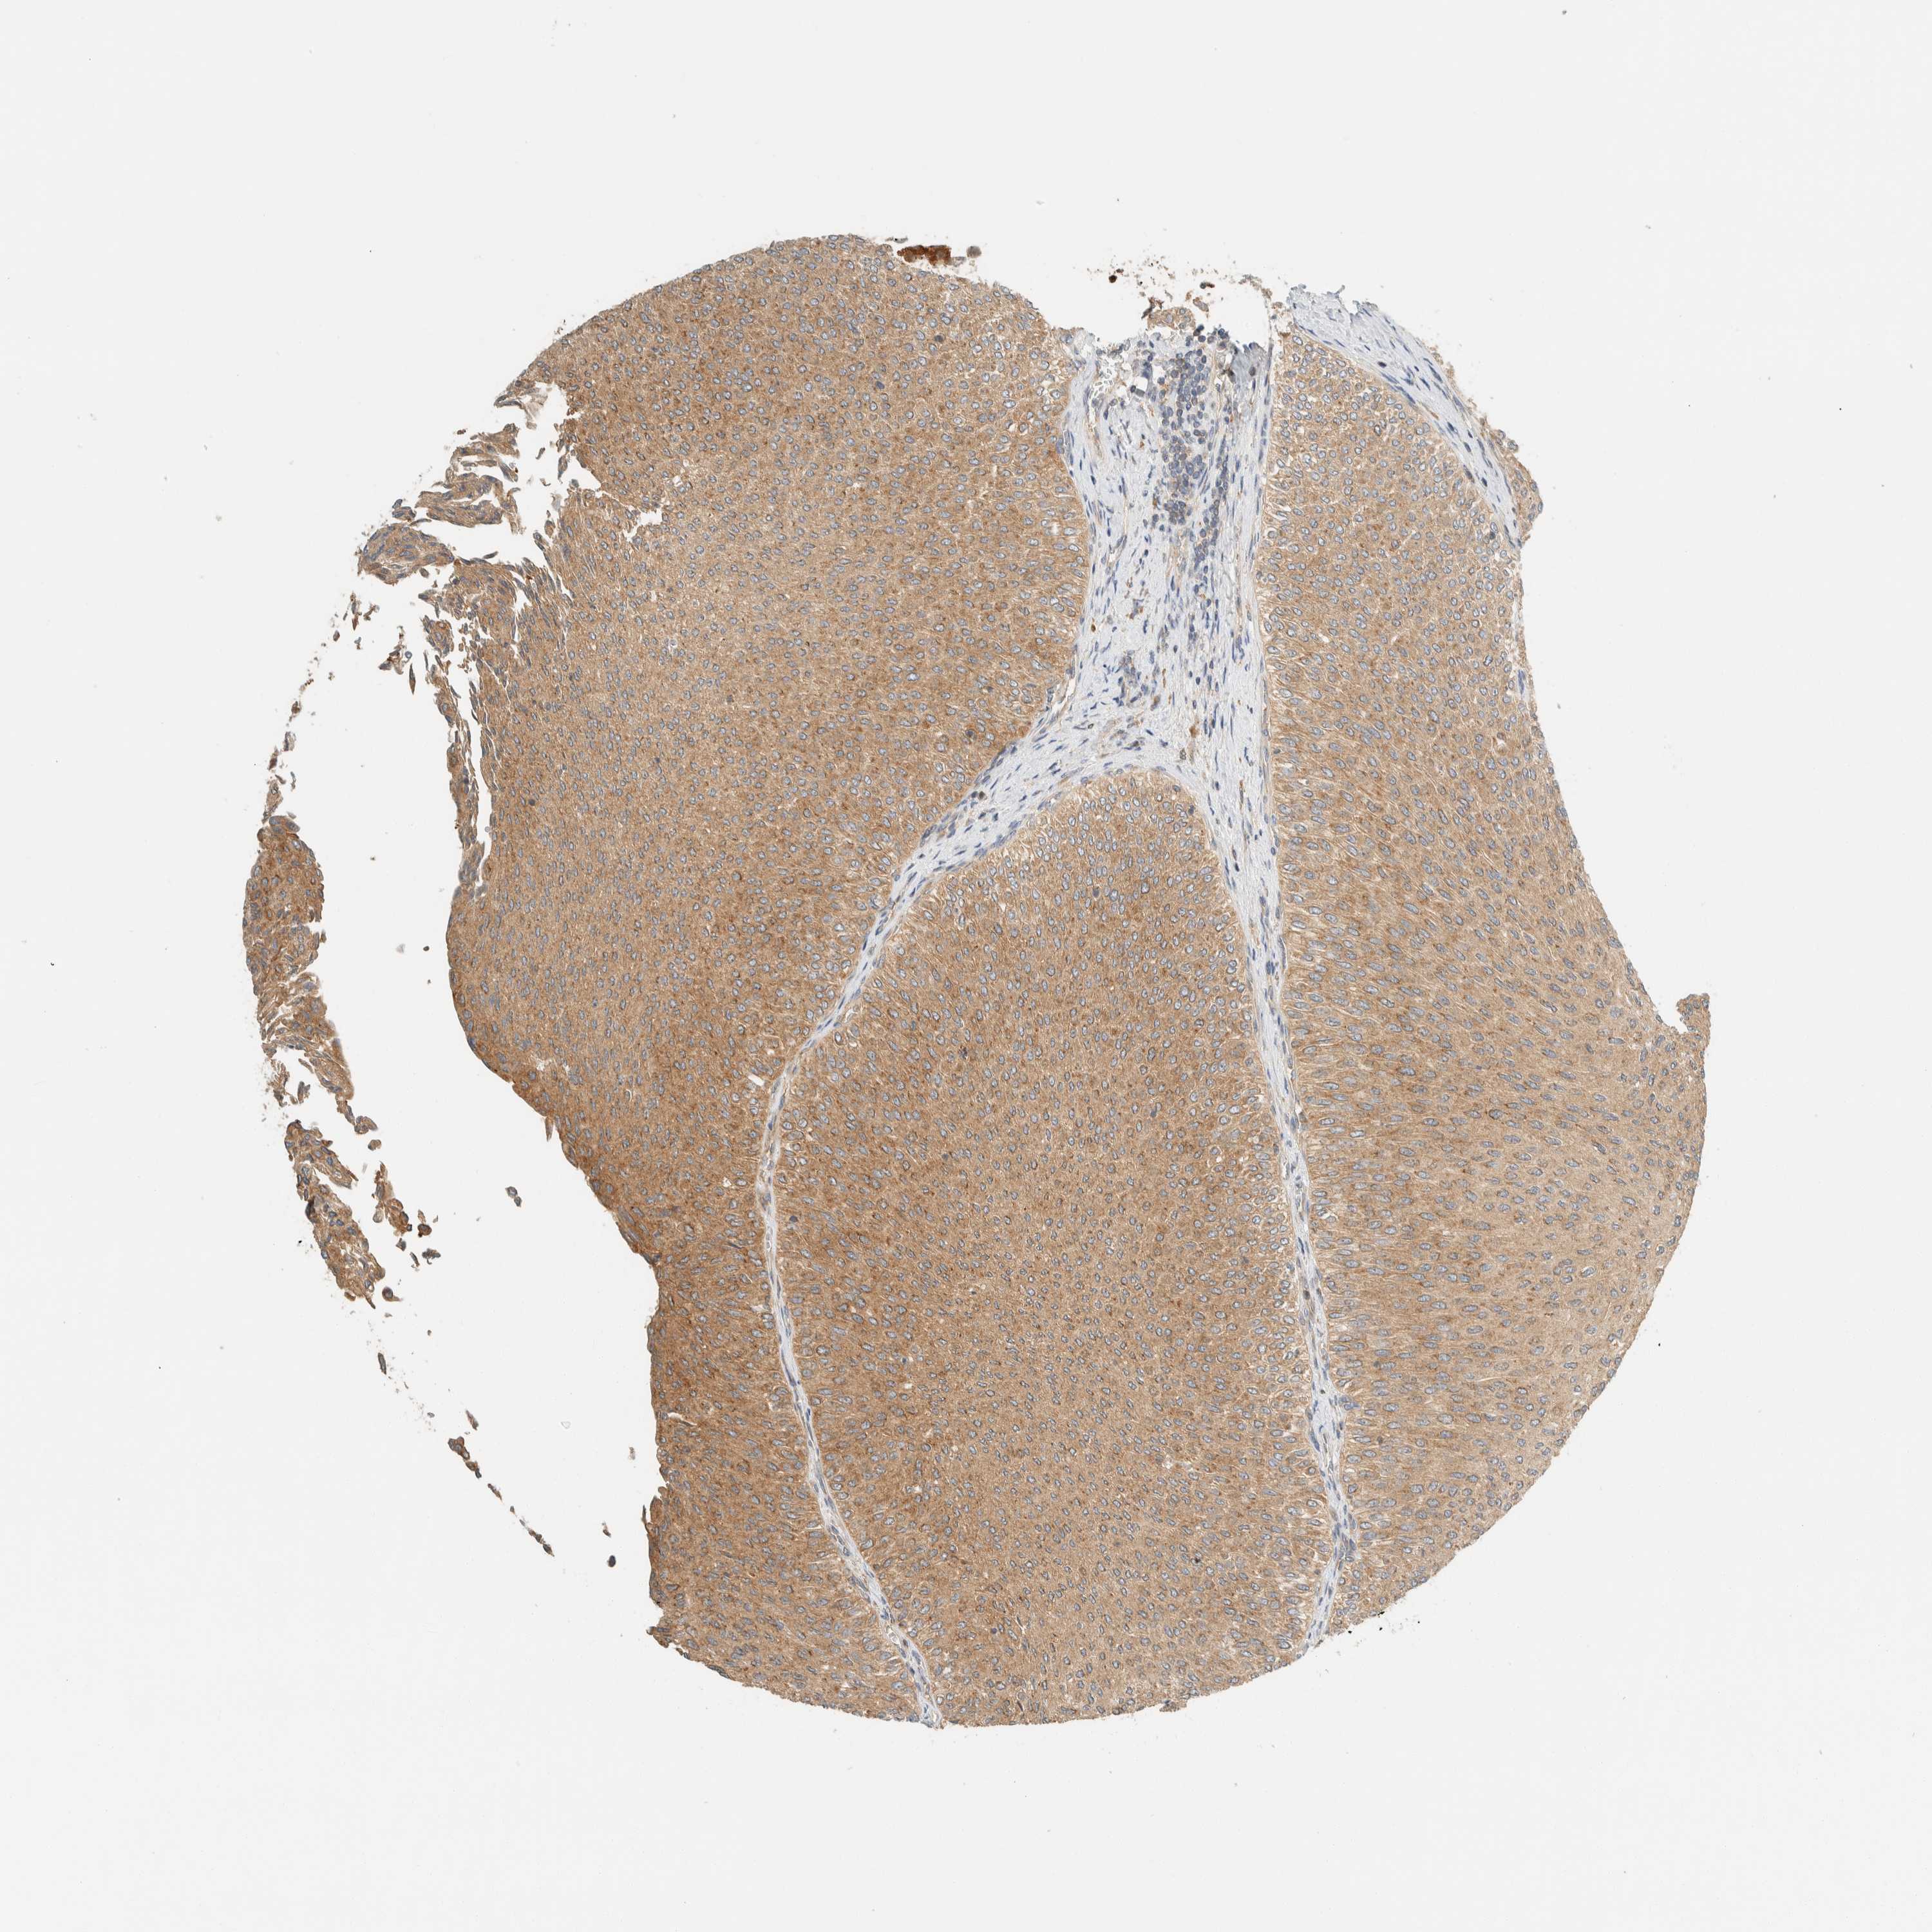

UROTHELIAL CANCER - Protein expressioni

A mouse-over function shows sample information and annotation data. Click on an image to view it in a full screen mode. Samples can be filtered based on level of antibody staining by selecting one or several of the following categories: high, medium, low and not detected. The assay and annotation is described here.

Note that samples used for immunohistochemistry by the Human Protein Atlas do not correspond to samples in the TCGA dataset.

Antibody stainingi

Antibody staining in the annotated cell types in the current human tissue is reported as not detected, low, medium, or high, based on conventional immunohistochemistry profiling in selected tissues. This score is based on the combination of the staining intensity and fraction of stained cells.

Each image is clickable and will lead to virtual microscopy that enables deeper exploration of all samples and also displays staining intensity scores, fraction scores and subcellular localization as well as patient and tissue information for each sample.

Antibody HPA023399

Antibody HPA023822

Urothelial carcinoma, Low grade

Urothelial carcinoma, High grade